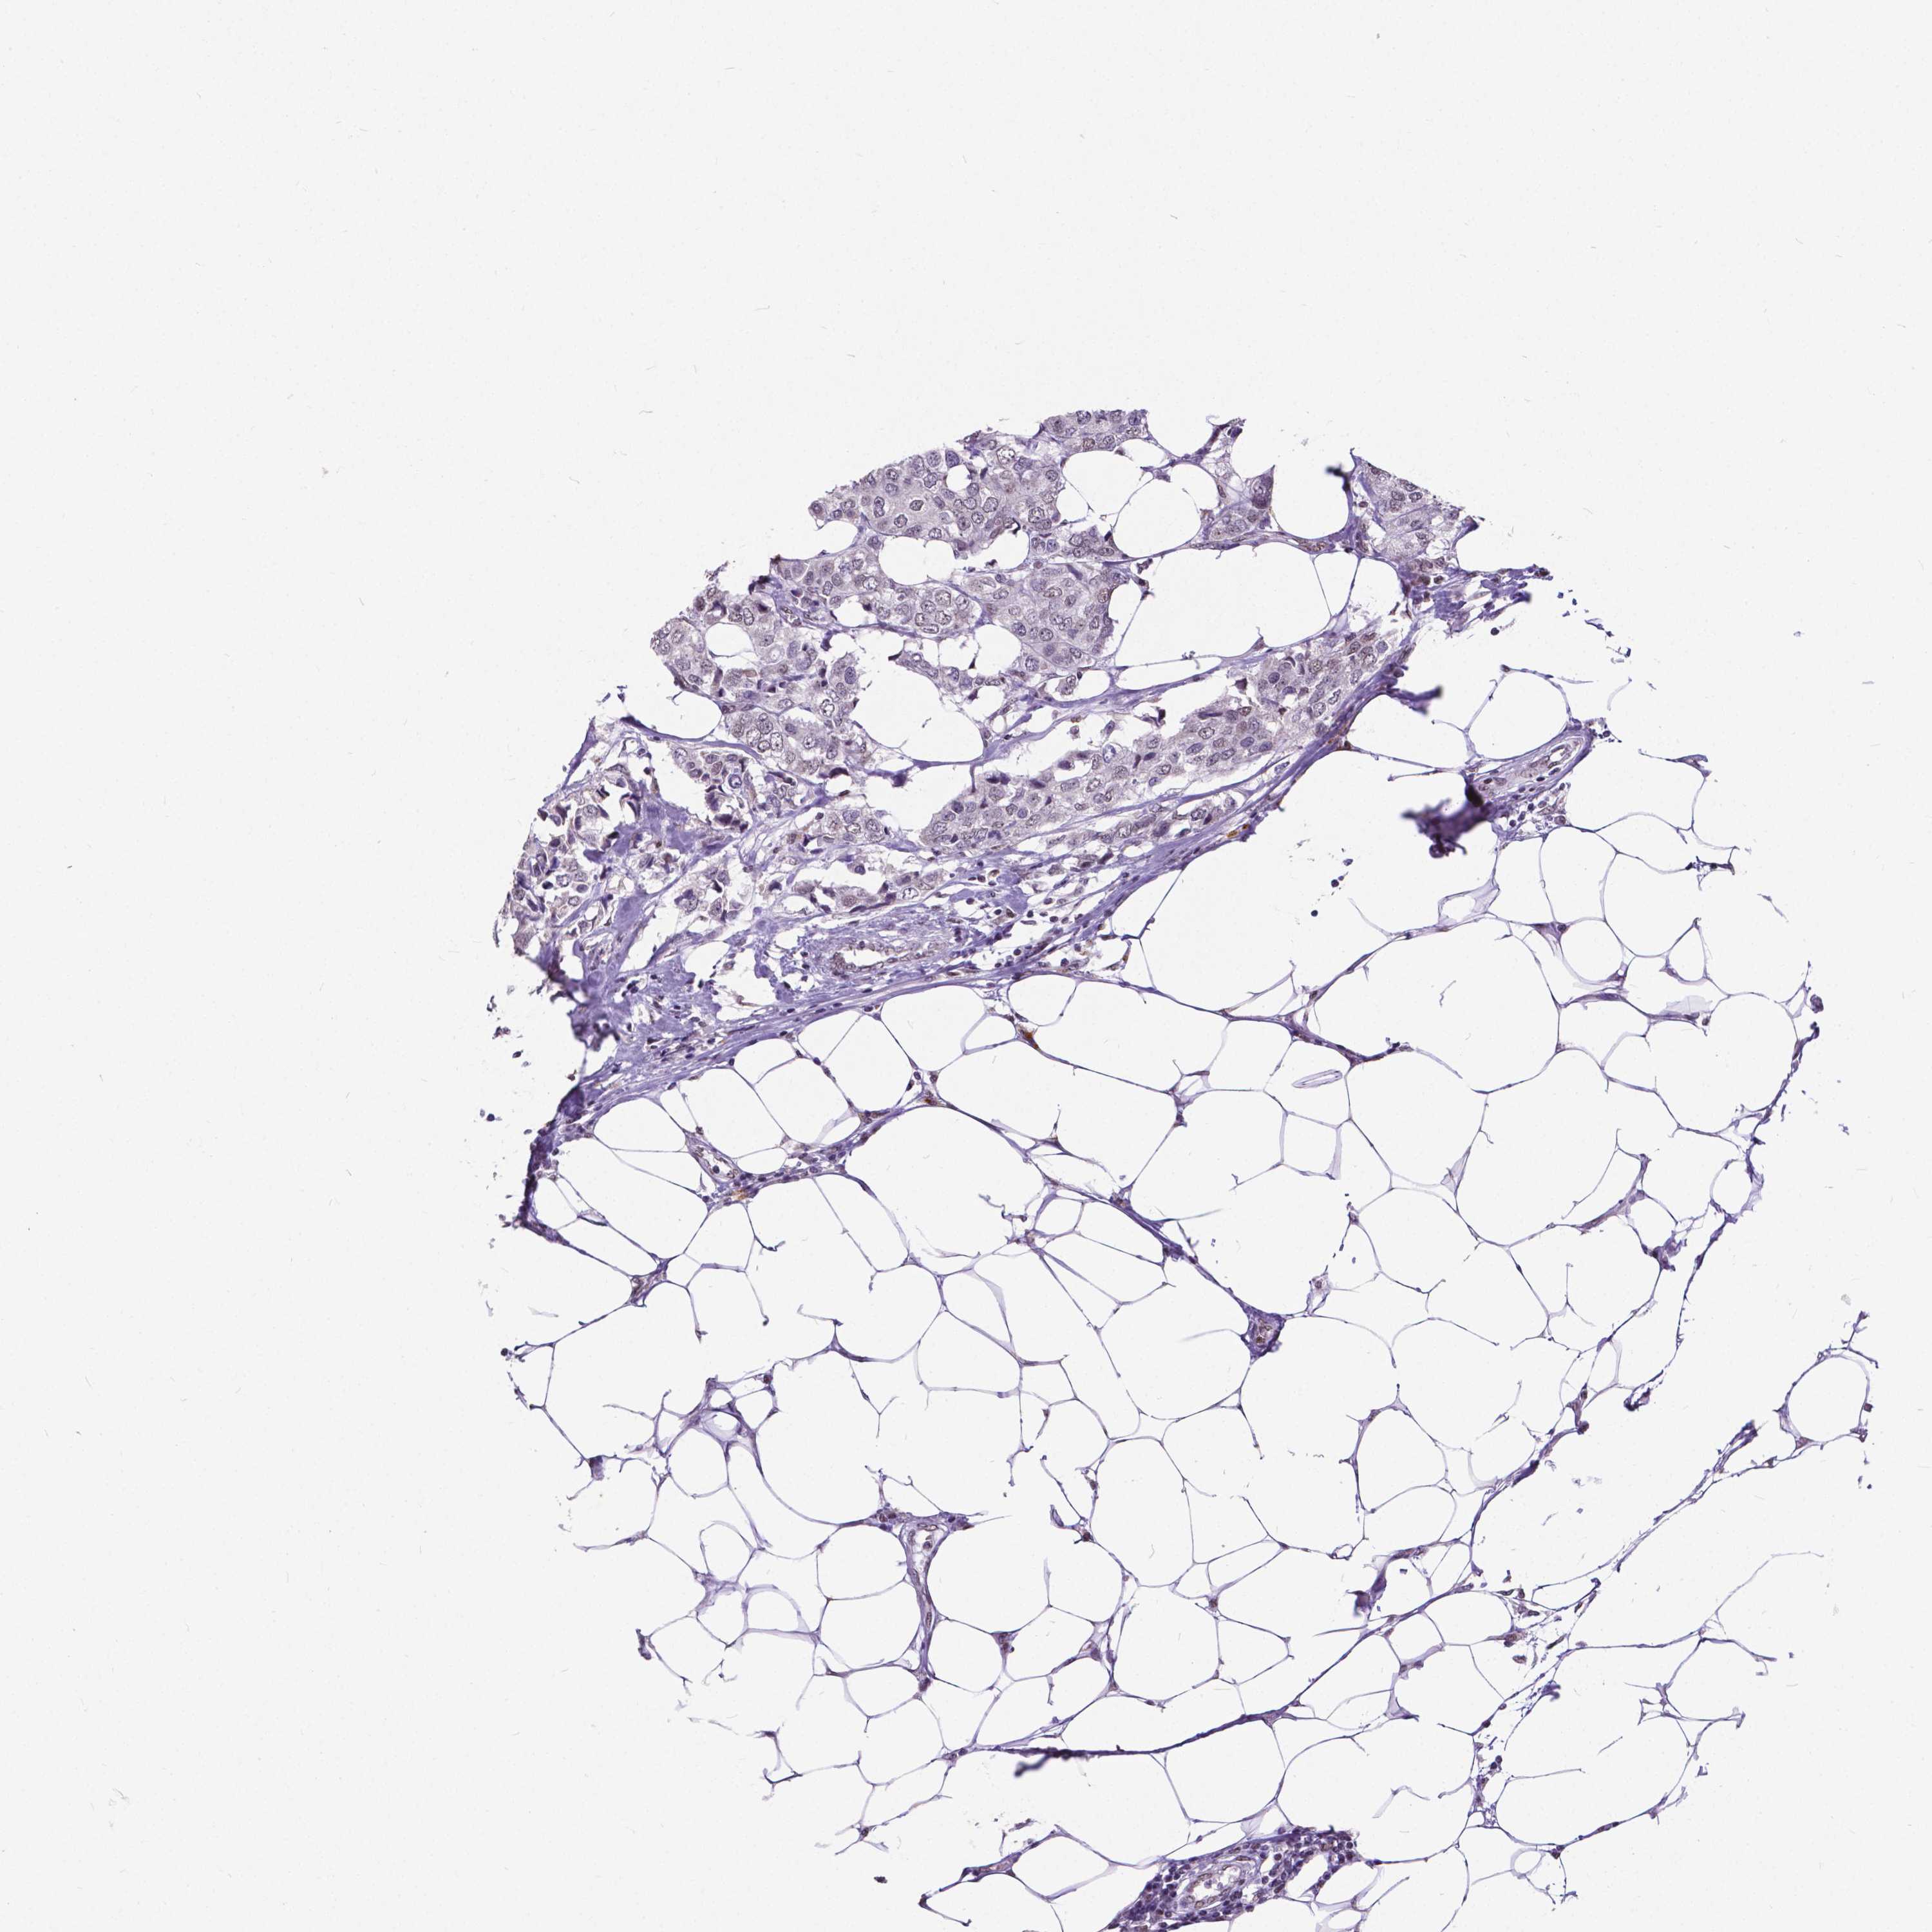

CANCER BREAST CANCER Show tissue menu

BRCA TCGA BRCA VALIDATION PROTEIN EXPRESSION